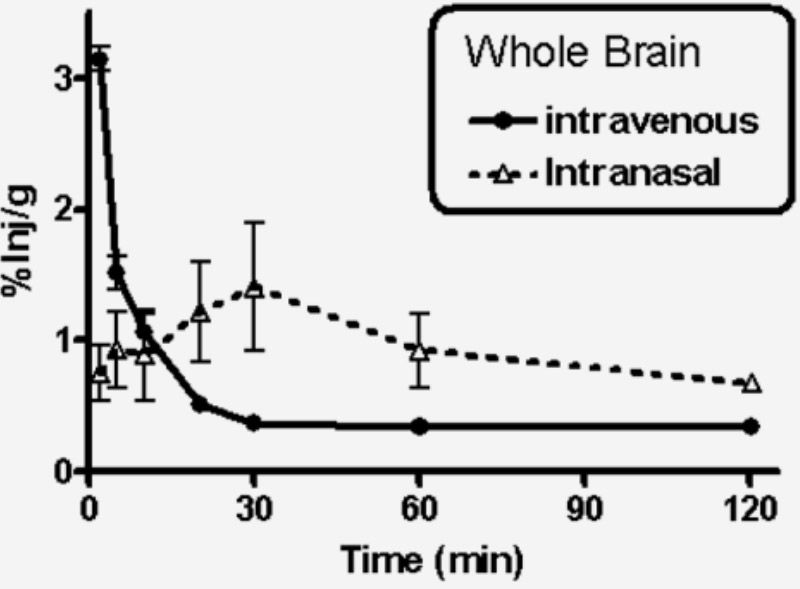

A pre-clinical study using the MetP technology for targeting the brain:

Compelling: The uptake of tritiated testosterone by the brain was about twice as high after intranasal administration as after intravenous administration.

Banks et al.: «About two-thirds of the testosterone entering the brain after i.n. [intranasal] administration did so by direct entry by nasal routes and the remainder indirectly by first entering the blood and then crossing the blood-brain barrier.»